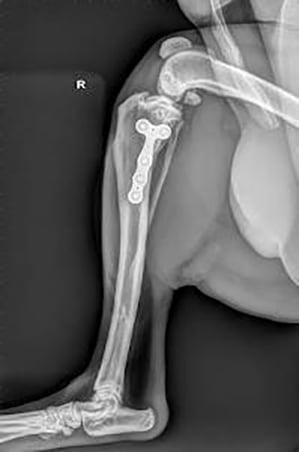

Un'opzione chirurgica sempre più usata è la TPLO (osteotomia del livellamento del piatto tibiale). Questa è una procedura molto più complessa rispetto al metodo tradizionale extracapsulare:la TPLO altera il meccanismo dell'articolazione del ginocchio, che permette di funzionare correttamente senza un legamento crociato. Viene eseguito un taglio nella parte superiore della tibia (plateau tibiale), poi il plateau tibiale viene ruotato per cambiare l'angolo e viene fissata una piastra metallica per mantenere l'osso in posizione. Nell'arco di diversi mesi, l'osso guarisce nella sua nuova posizione. Un parziale miglioramento può essere visto in pochi giorni, tuttavia, per il pieno recupero occorrono diversi mesi ed un periodo di permanenza in gabbia è essenziale. In generale, la prognosi a lungo termine è molto buona, e il re-infortunio è raro. Il piatto non ha bisogno di essere rimosso a meno che non si verifichino problemi in seguito.